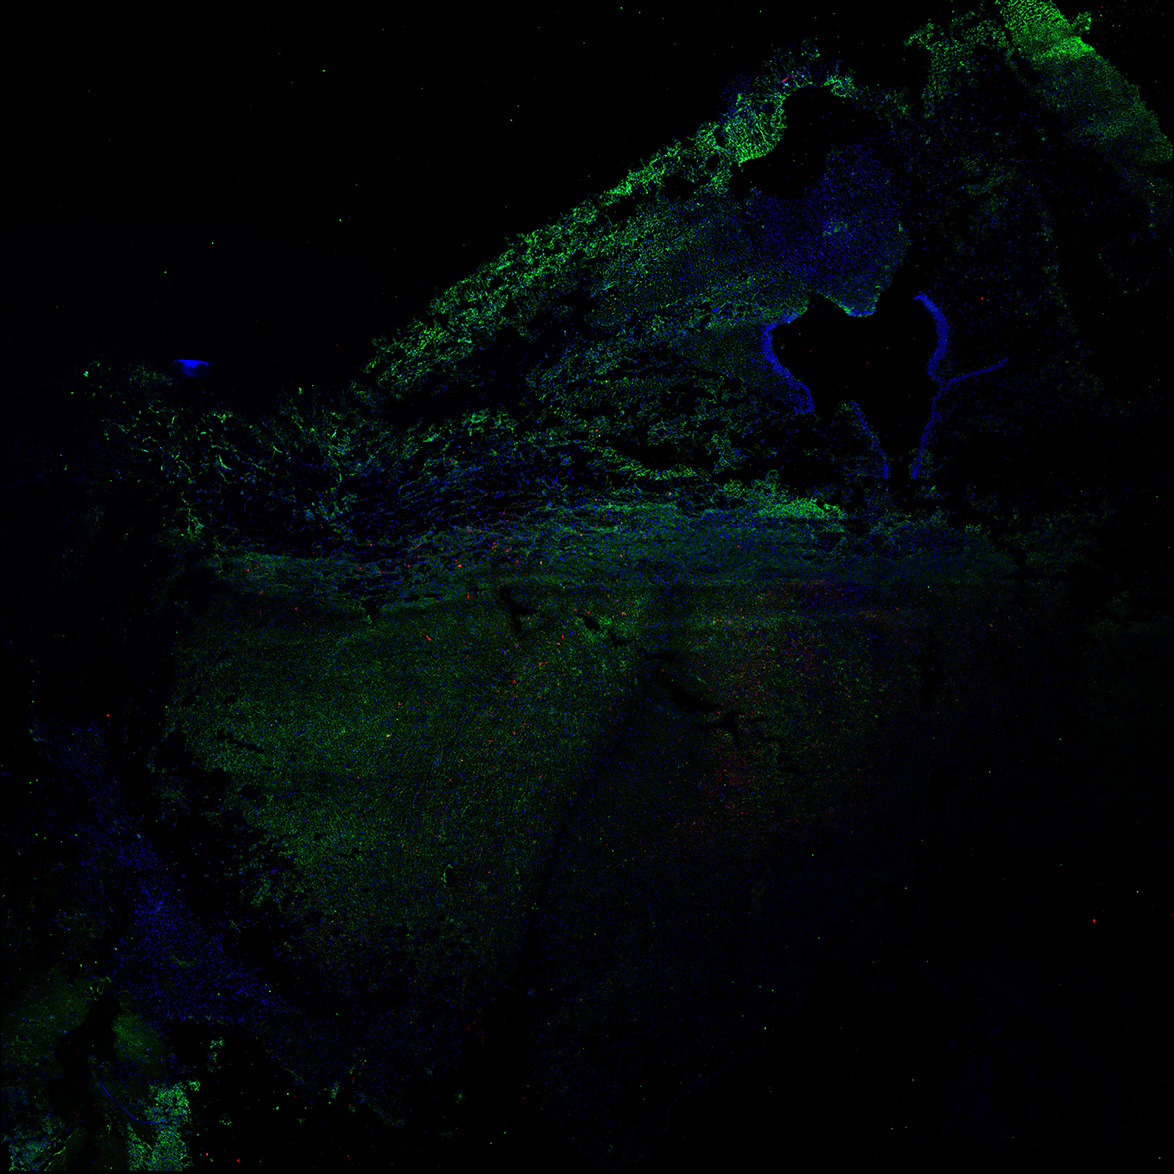

An anatomical analysis of the developing human midbrain from 6 post-conceptional weeks (PCW) to 22 PCW reveals increased tissue complexity, characterized by the emergence of dopaminergic nuclei, as highlighted by immunofluorescence analysis for tyrosine hydroxylase (TH).

MAP2

7PCW human midbrain

TH

Merged